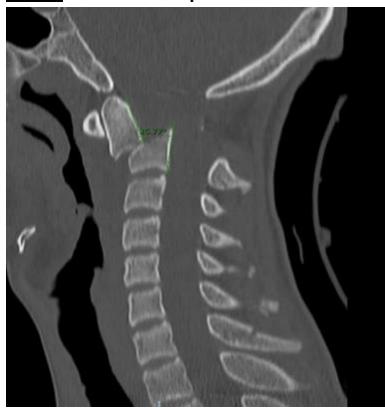

You are evaluating a 17 years old adolescent girl who was in an unrestrained motor vehicle accident. Imaging is demonstrated. And she has significant posterior midline neck pain. What is the diagnosis and MOI?

- Jumped facet Hyperflexion